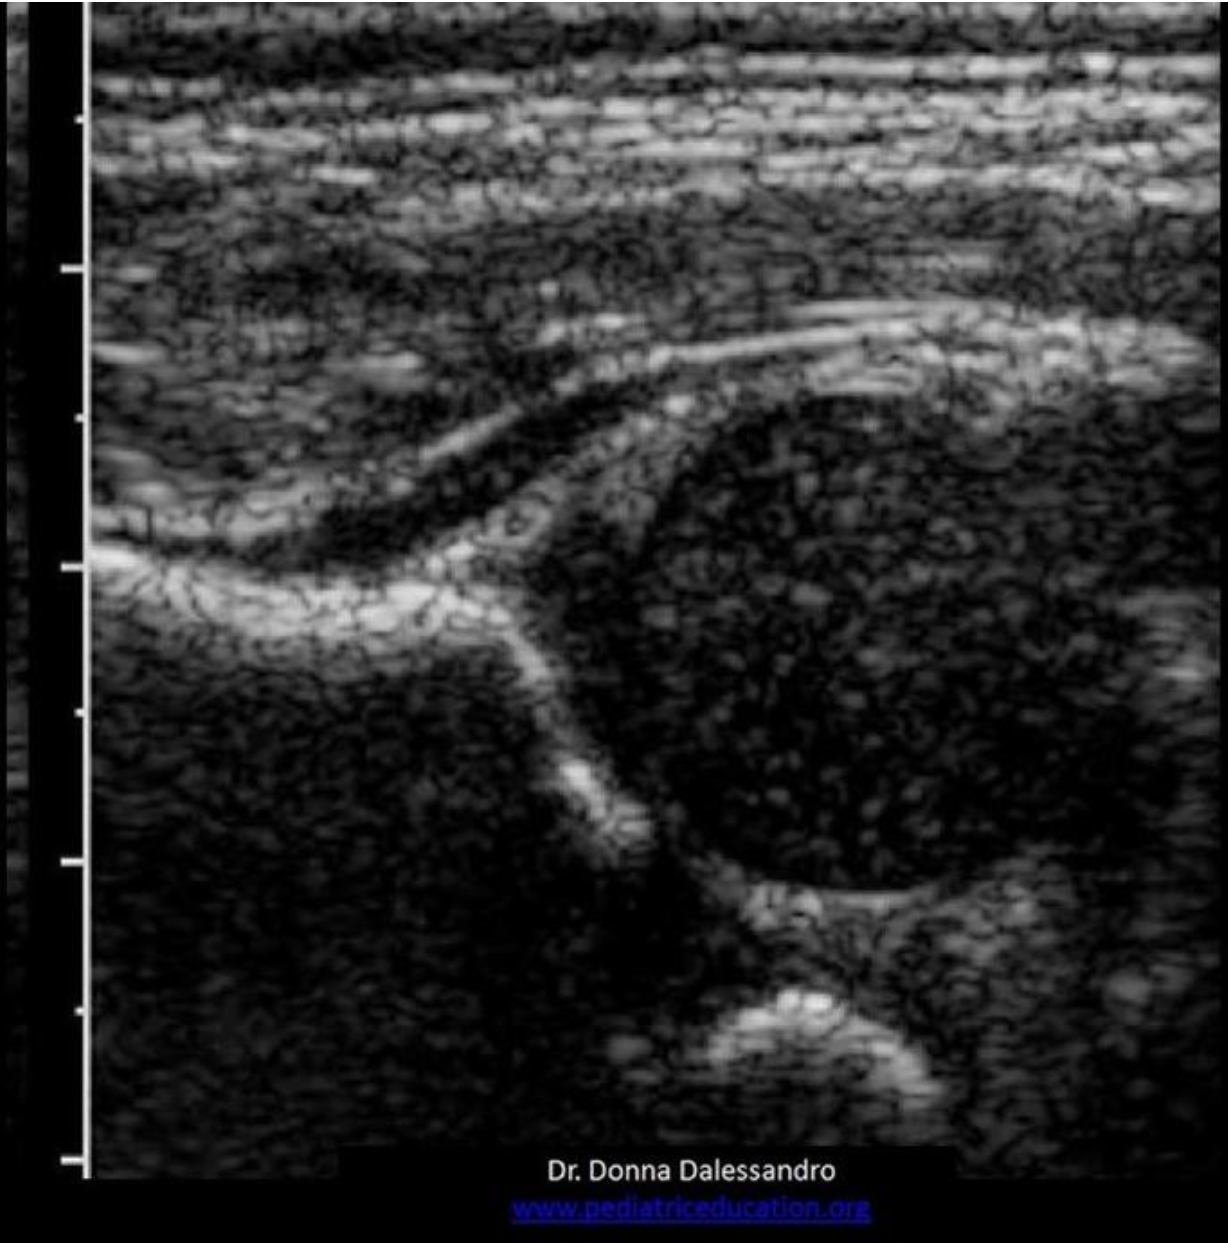

Which of the following is synthesized by the adrenal medulla?

B. Epinephrine

The adrenal cortex synthesizes cortisol, androgens, estrogen, progesterone and aldosterone. The adrenal medulla synthesizes catecholamines (epinephrine, norepinephrine).